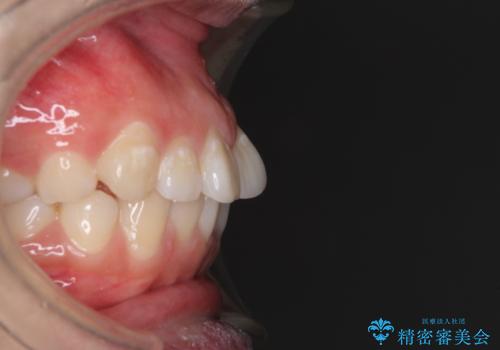

当初は口元の突出感はあまり気にされていない様子だったので、インビザラインによる非抜歯矯正をお勧めしたが、ふっくらとした口元を改善したいとのことで、積極的に口元の突出感を改善することとしました。

上下左右第一小臼歯4本の抜歯を行い、ワイヤー装置による矯正治療を行うこととしました。

横顔の印象が大きく改善され、患者様には大変満足していただきました。